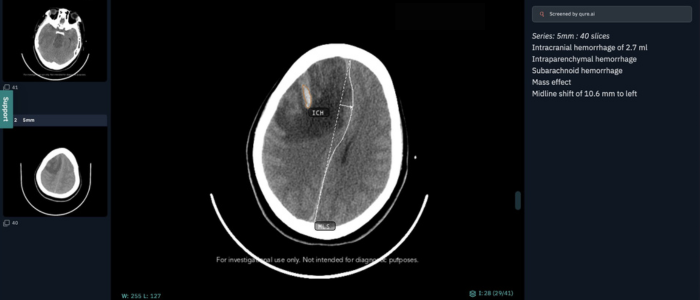

The trial, which utilises the qER head CT Artificial Intelligence (AI) solution from Qure.ai, seeks to improve radiology report turnaround times for non-contrast CT head scans by creating prioritised reporting worklists of critical findings. This will allow Emergency Department (ED) clinicians to make faster decisions about the care, management and discharge of patients with head injuries.

In the first few weeks of its implementation over the 2023/24 winter period, qER analysed 651 non-contrast head CTs, detecting 128 potentially critical findings including cranial fractures, intracranial haemorrhage (ICH), mass effect and mid-line shift within the brain.